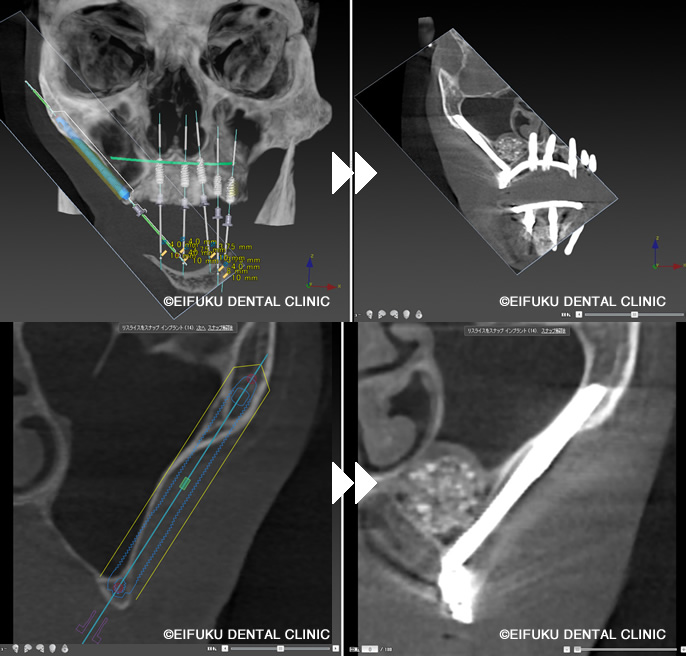

| コメント | 「歯がボロボロで、このままでは何も噛めない」とお悩みの高齢70代のの女性の患者さんが、東京都内でインプラント治療を探されて当院に来院されました。 長年のむし歯と歯周病により、上も下もご自身の歯ではほとんど噛めない状態で、「入れ歯は合わないのですぐにしっかり噛みたい」というのが一番のご希望でした。当院ではまずCTによる精密検査を行い、骨量が大きく失われていた上顎には通常のインプラントではなく、頬骨を利用するザイゴマインプラントを選択しました。 下顎には4本のインプラントで全体の歯を支える「オールオン4(All-on-4)インプラント」を計画し、噛み合わせや負担のバランスを綿密に設計したうえで手術に臨みました。「手術が怖い」「痛みが心配」という不安をお持ちだったため、点滴でお薬を入れてうとうとリラックスした状態で治療が受けられる「静脈内鎮静法」を併用しました。 全身麻酔とは異なり意識は保ちながらも、手術中の恐怖心や痛みの記憶がほとんど残らず、長時間のインプラント手術でも安心して受けていただける方法です。手術当日に上顎ザイゴマインプラントと下顎オールオン4のインプラントを埋入し、十分な初期固定が得られたため、その日のうちに固定式の仮歯を装着しました。 「久しぶりに自分の歯で噛めているような感覚」「手術の記憶もあまりなく、あっという間に終わった」と、柔らかいものから少しずつお食事を楽しんでいただけるようになりました。ザイゴマインプラントやオールオン4は、総入れ歯や「歯がボロボロ」でお困りの方、骨が少なく他院でインプラントが難しいと言われた方でも、しっかり噛める状態を目指せる高度なインプラント治療です。 当院ではインプラント専門の歯科医師が、静脈内鎮静法を用いた負担の少ない手術と、長期的なメインテナンスまで見据えた治療計画で、東京都エリアの患者さんの「すぐに噛みたい」という願いにお応えしています。 |

通常、インプラント手術の際に、歯肉を切開し、歯肉とあごの骨にインプラントを埋め込むする穴を開ける工程があります。その際に専用のドリルを使用するのですが、骨が細かったり、0,1mm単位で正確に埋入が必要な場合、サージカルガイドシステムが役立ちます。